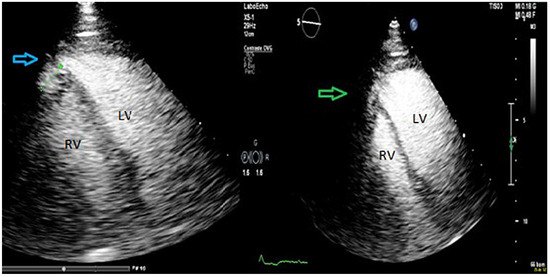

Sinus Venosus and Unroofed Coronary Sinus Defects: Two Cases Diagnosed and Treated in Adulthood

by Karimzadeh Soran, Sologashvili Tornike, Myers Patrick O., Hachulla Anne-Lise, Lador Frederic, Bouchardy Judith and Noble Stephane

Interatrial communications are the most frequent congenital heart malformation in adulthood. Four different types of atrial defect are identified: the ostium secundum, ostium primum, sinus venosus and unroofed coronary sinus types. The unroofed coronary sinus defect is the rarest form of interatrial communication [...] Read more.

Interatrial communications are the most frequent congenital heart malformation in adulthood. Four different types of atrial defect are identified: the ostium secundum, ostium primum, sinus venosus and unroofed coronary sinus types. The unroofed coronary sinus defect is the rarest form of interatrial communication accounting for <1% overall. The presence of a persistent left superior vena cava is frequent in this form of atrial defect and associated anomalous pulmonary venous return has been described. The sinus venosus form – accounting for 5 to 10% of atrial defects – is a communication between the two atria localised within the mouth of the caval vein, which has a biatrial connection. It most frequently involves the superior vena cava and anomalous pulmonary venous return (usually the right upper pulmonary vein) and is associated with 85% of atrial defects. We report typical examples of sinus venosus and unroofed coronary sinus defects associated with anomalous pulmonary venous return. Full article